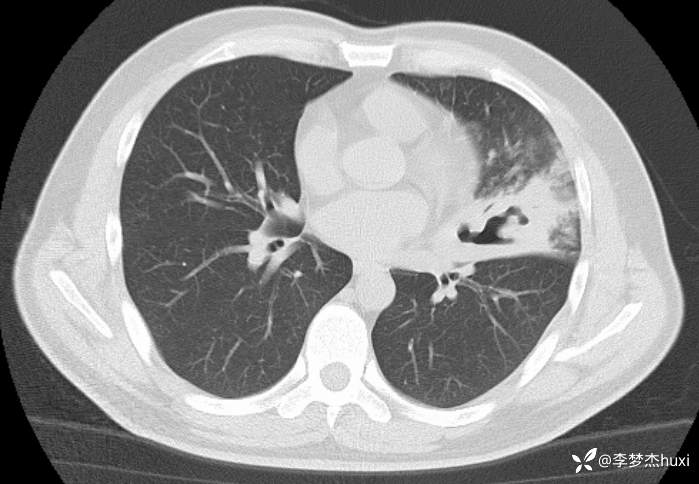

男性40岁,咳嗽、咳痰5天,CT示空洞病变,可能是啥病原菌?

【现病史及既往史】: 1.患者中年 男,患者缘于5天前前无诱因出现咳嗽、咳痰,为黄痰,伴臭味,痰不易咳出,伴发热,最高体温不详,无喘息、憋气,无胸痛,无咯血,无腹痛腹泻,无恶心、呕吐。院外未应用药物治疗,症状无明显好转,为求进一步治疗来院就诊,门诊查胸部CT;双肺炎症,左肺上叶厚壁空洞形成,双肺纹理增重,双侧胸膜局限性增厚,脂肪肝,建议结合临床复查。以“肺炎”收住院;。

【临床诊断】:肺脓肿伴有肺炎。